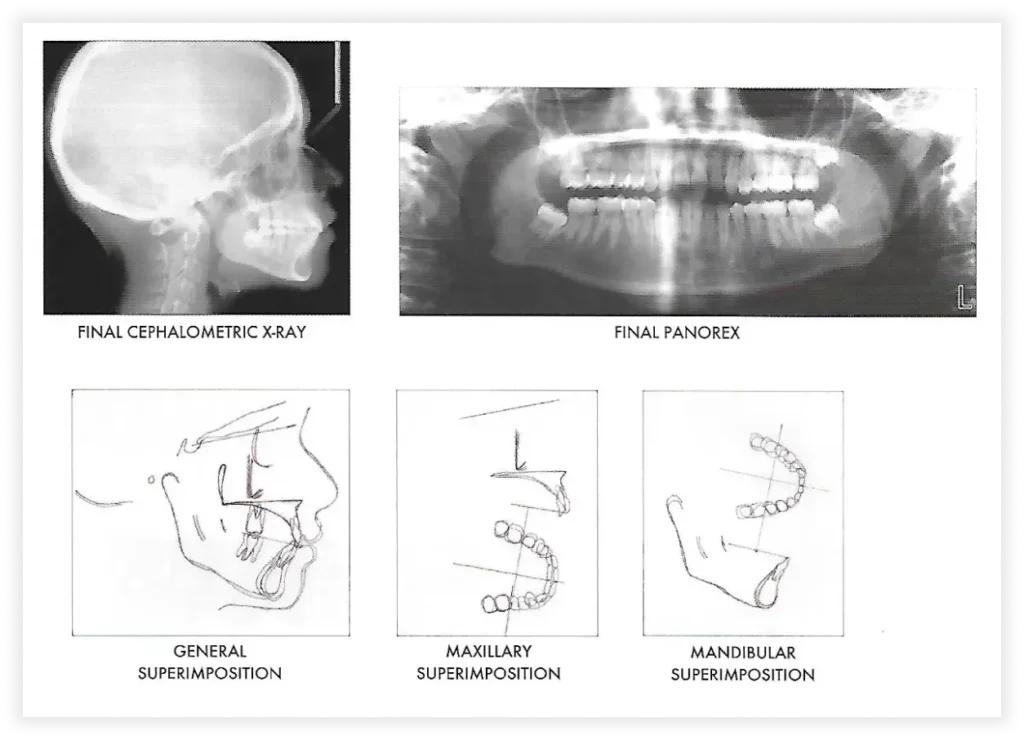

Smile Gallery

Take a look at some of our cases and successful transformations below.

Case #3

Initial Photos

Final Photos